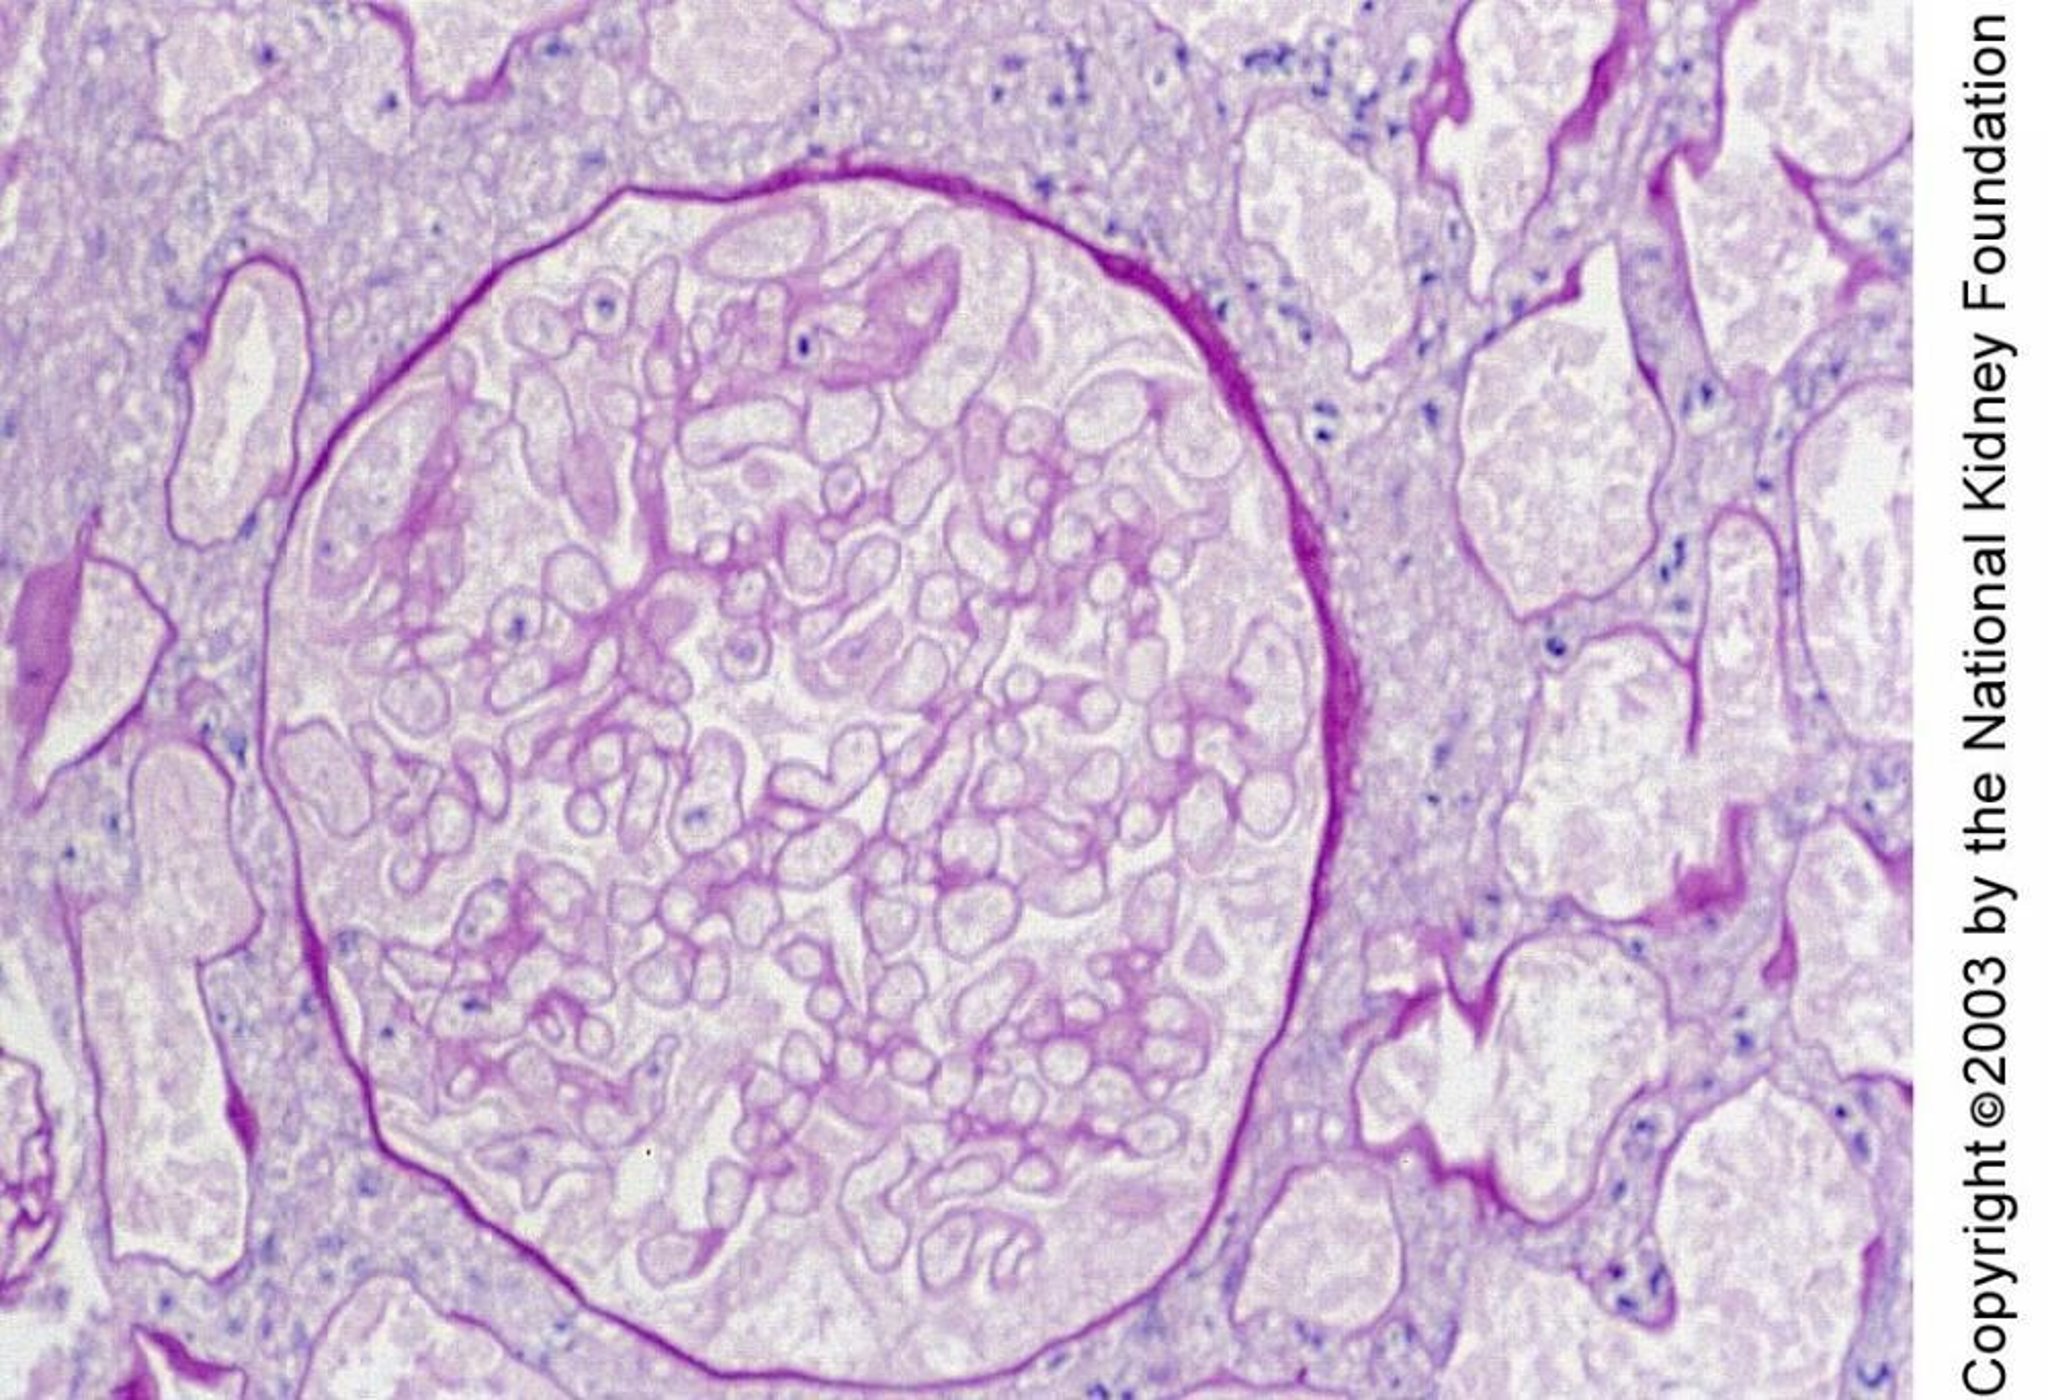

Necrosi corticale renale

La necrosi corticale renale è caratterizzata istologicamente da necrosi di glomeruli e tubuli. La necrosi in questo campione bioptico si evince dai gruppi di cellule con nuclei piccoli e cellule fantasma (colorazione con acido periodico di Schiff, × 400).

Imagine fornita da Agnes Fogo, MD, and the American Journal of Kidney Diseases' Atlas of Renal Pathology (vedi www.ajkd.org).